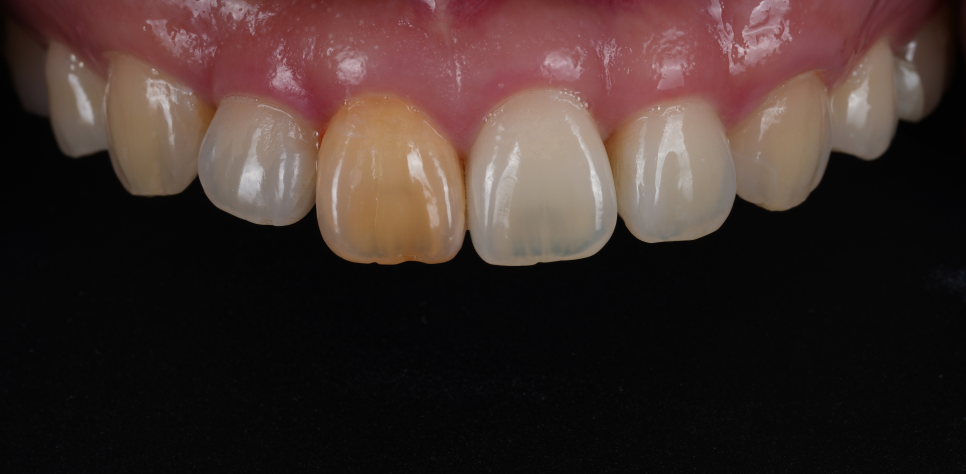

사진부터 보여드릴게요.

촬영일 : 250905

오래전, 외상으로 인해

신경이 죽으면서 앞니가 심하게

변색되었는데요.

타치과에서는

이렇게 진단받으셨다고 합니다.